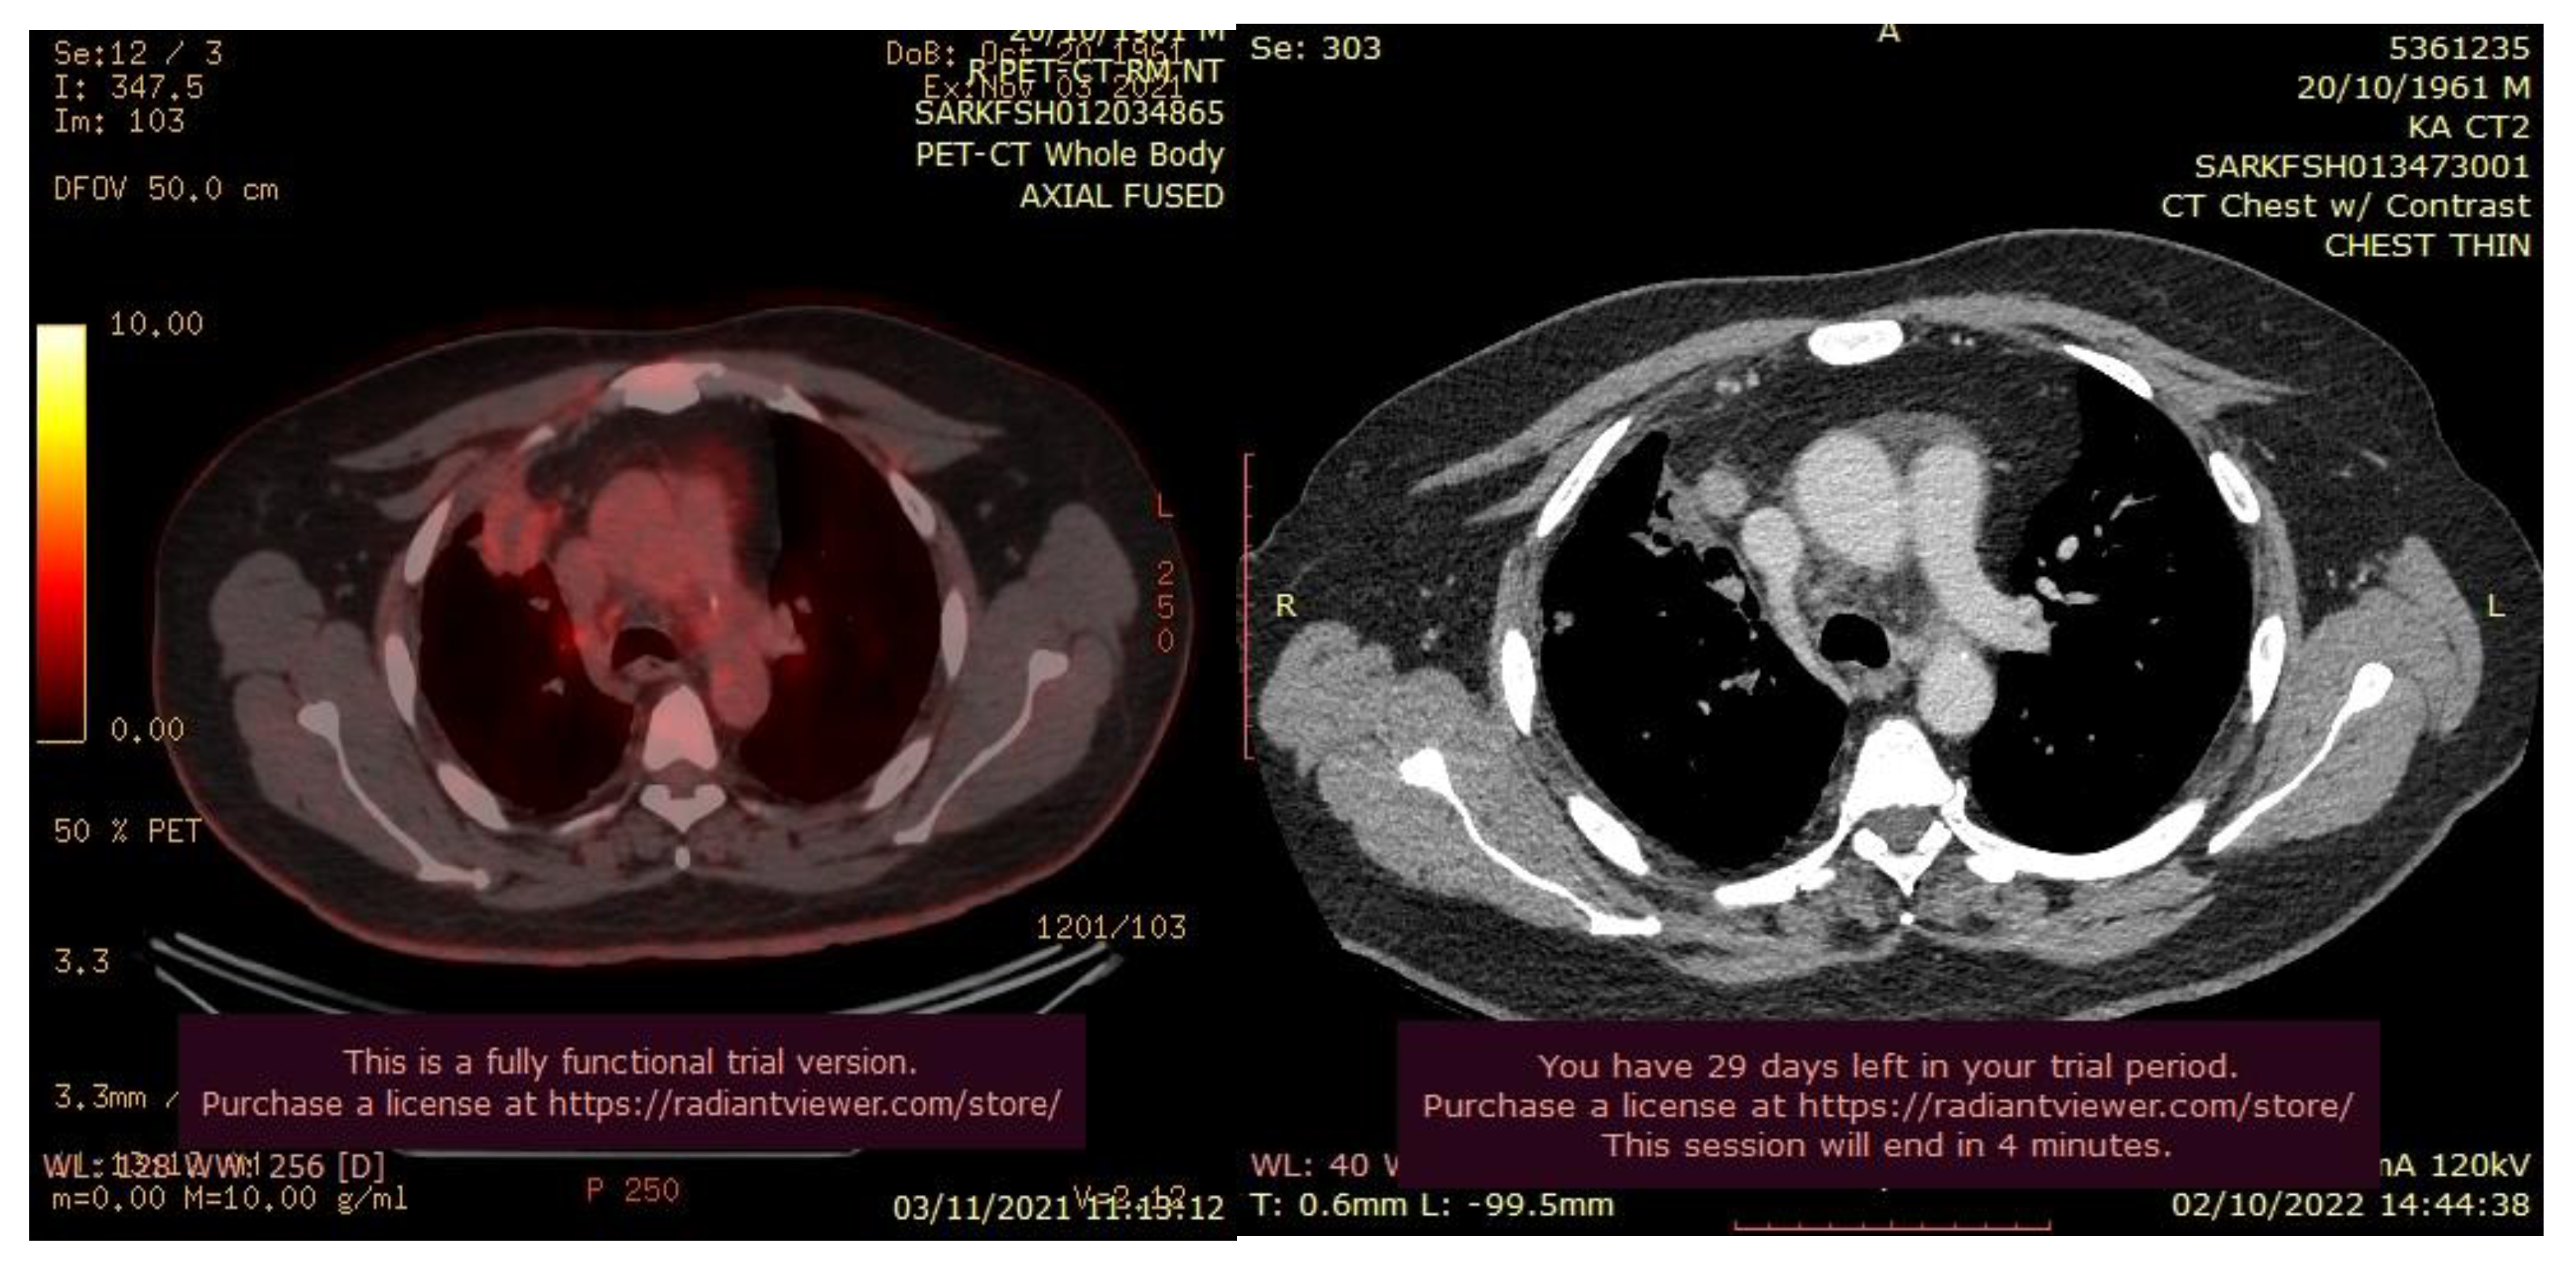

The patient’s history and physical examination as well as recent imaging evaluation should be well evaluated. Chest CT is the key imaging modality for evaluating lung tumor size and the location of lesions. Because of the complaint also of dysphagia, we conducted a CT scan of the chest, abdomen, and pelvis with means of contrast. A biopsy was taken as advised by [52]. The presence of small cell lung cancer, stage IVA (T4 N3 M1a) was confirmed. PET-CT and CT scans show images of a hypermetabolic left pulmonary hilar tumor (Figure 2).

Figure 2. CT scan (left) and Pet-CT (right) images of hypermetabolic left pulmonary hilar tumor from a female SCC patient.